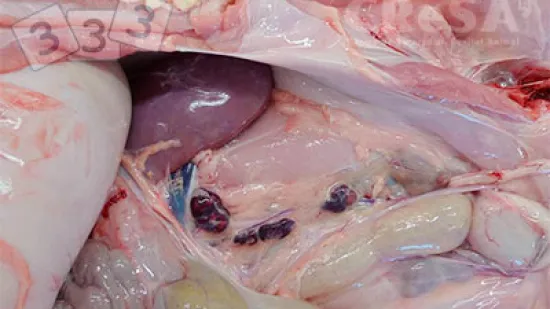

Semaine du 26-Jul-2021

Quelle est la cause la plus probable de cette lésion hépatique ?